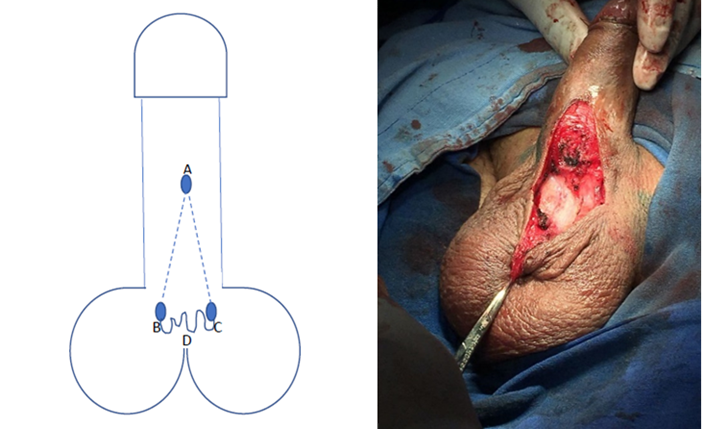

Se realiza protocolo prequirúrgico con documentación completa en el expediente clínico, ingreso del paciente para cirugía ambulatoria, con valoración anestésica, ayuno de 8 horas, baño previo al procedimiento, no se administró antibiótico profiláctico por no estar justificado, se realiza tricotomía según se necesite, se aplica asepsia antisepsia con iodopovidona. Se coloca lidocaína al 2% como anestésico local en el área quirúrgica en planos superficiales y profundos. La técnica quirúrgica aplicada en ambos casos se trata de una Plastia V-T, la cual consiste en realizar una incisión sobre la cuerda en forma de v invertida para despegar las capas de la piel de su adherencia aberrante en la cara ventral del pene (Figura 1 y 2), se afronta la nueva base del pene con sutura absorbible (Figura 3 y 4) , posteriormente se realiza incisiones laterales a la base del pene y coincidiendo a la raíz de la piel del escroto para distribuir toda la piel escrotal sobrante de manera uniforme, esto confiere la forma final de una T invertida (Figura 5 y 6).

Figura 3 Se realiza la incisión desde A a B y A a C, disecando las adherencias de la cuerda hasta la base del pene, quedando la piel del escroto redundante D.

Figura 4 Se sutura B con C para formar la nueva base del pene en su cara ventral y afrontando el resto de la piel del trayecto A con B-C, quedando la piel redundante, D, debajo.

Podemos observar que posterior a la realización de la circuncisión, se realizó paso a paso la técnica propuesta como podemos observar en las Figuras 1-6 que corresponden al caso 1 que fue el más representativo de la técnica.